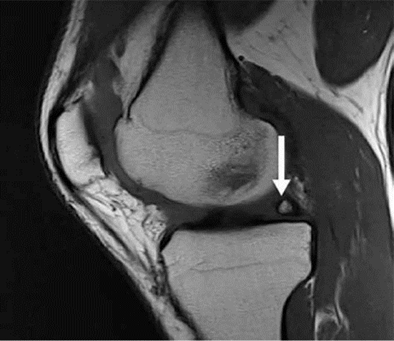

Hình 6. Nốt sần sụn chêm. Hình ảnh pd sagittal cho thấy một nốt sần hình sụn (mũi tên) ở vùng của rễ sụn trung gian sừng sau.